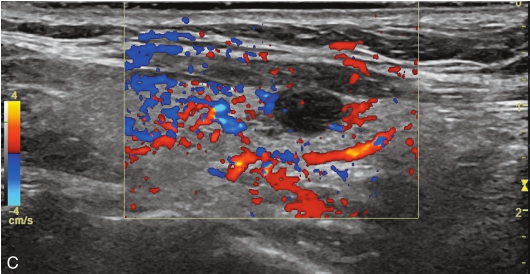

甲状腺左叶中下部见一混合回声结节,边界清,形态规则,中心部可见斑状强回声,CDFI显示周边可见环状血流信号,其内可见丰富血流信号,见图1-3-18。

该结节早于周围腺体组织增强,结节内部呈高增强表现,可见部分无增强区;结节晚于周围腺体组织消退,仍呈高增强表现;结节周边可见均匀高增强环,甲状腺被膜未见明显中断,见图1-3-19、ER1-3-9。

图1-3-18 甲状腺滤泡性腺瘤常规超声声像图

A.甲状腺左叶纵切面超声图像;B.结节内部点状及斑状强回声;C.CDFI血流图

图1-3-19 甲状腺滤泡性腺瘤超声造影图

A.注入造影剂后9s;B.注入造影剂后11s;C.注入造影剂后16s;D.注入造影剂后27s

(1)结节增强早期早于腺体增强或与腺体同步增强,增强晚期晚于腺体消退或与腺体同步消退。

(2)结节内部呈均匀或不均匀弥漫性等增强或高增强,增强水平通常高于周围腺体。

(3)结节与周围腺体分界清晰,形态较规则。

(4)部分结节周边可见均匀高增强环。

(5)结节周边被膜连续完整。

甲状腺滤泡性腺瘤通常为富血供病灶,其增强水平等于或高于周围腺体,并呈现“早增强,晚消退”的特点,重点需要与滤泡性腺癌鉴别,腺瘤多边界清晰、形态较规则,造影时结节周围的高增强环厚薄一致、较为均匀,结节周边被膜连续完整、无浸润表现,颈部淋巴结无异常肿大等。而滤泡性腺癌边界不清、呈浸润性生长表现,周边高增强环消失或厚薄不均,如发现颈部异常肿大淋巴结及被膜连续性中断等,需要高度警惕甲状腺恶性肿瘤。